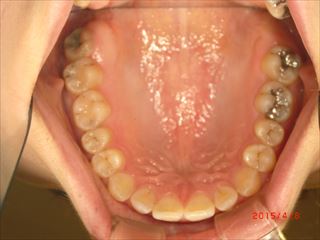

施術前

CIMG4912 R

施術後